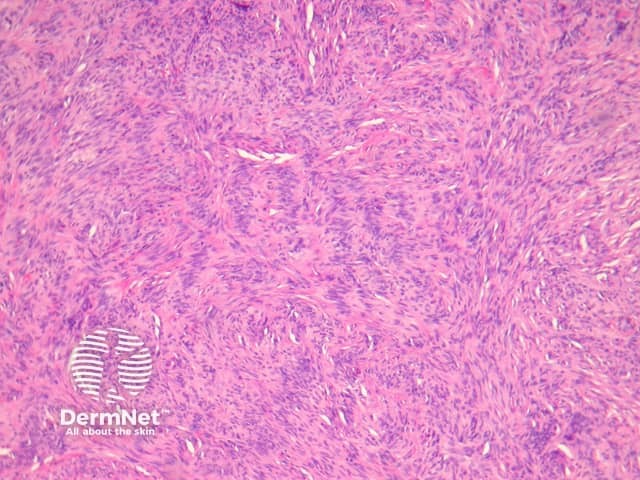

Compared with usual dermatofibroma, cellular dermatofibroma has an increased chance of recurrence following excision and metastasis is reported. Histologically, there is increased cellularity with a swirling, storiform pattern (figures 3,4). Peripheral entrapment of collagen is less prominent in this variant. There may be increased mitoses and extension to the subcutaneous fat, which are associated with more aggressive behaviour. Approximately 10% of cases show central necrosis.

Cellular dermatofibroma may resemble dermatofibrosarcoma protuberans, which can be differentiated by its larger size, increased mitoses and marked involvement of the subcutis. CD34 is positive in dermatofibrosarcoma protuberans and is usually negative in dermatofibroma, although the cellular variant may have focal positivity, especially at the periphery of the lesion. A study of clonal karyotype abnormalities in dermatofibroma found cellular dermatofibromas were more likely to have karyotype abnormalities than common dermatofibromas.